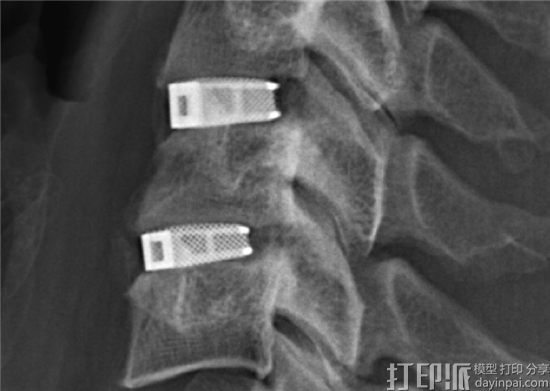

德国医疗器械公司Emerging Implant Technologies(EIT)的3D打印CellularTitanium®脊柱支撑植入物现已获得美国食品和药物管理局(FDA)批准。

迄今为止,EIT开发的Cellular Titanium植入物已经用在了来自15个国家的10000个病例中。FDA批准允许EIT首次在美国销售这种椎间融合器,这是EIT的一个重要里程碑。

Cellular Titanium是用选择性激光熔融(SLM)增材制造而成的,有80%的孔隙率,极大促进了骨修复所需的细胞生长。此外,如果研究发现了能优化孔隙率或植入物设计的新参数,SLM将允许EIT轻松重新设计设备并重新申请批准。